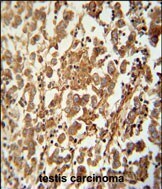

- Main image

- Experimental details

- Immunohistochemistry analysis of SPATC1 in formalin fixed and paraffin embedded human testis carcinoma. Samples were incubated with SPATC1 polyclonal antibody (Product # PA5-24120) followed by peroxidase conjugation of the secondary antibody and DAB staining. This data demonstrates the use of this antibody for immunohistochemistry. Clinical relevance has not been evaluated.